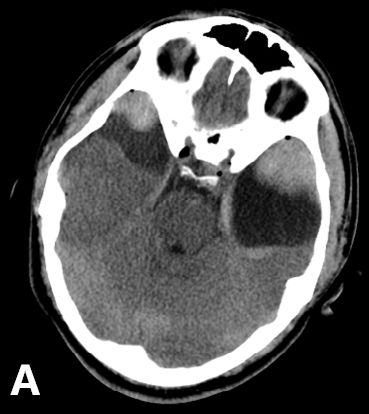

25岁男性患者,有双侧颞部蛛网膜囊肿,因醉驾而发生车祸。入院时GCS评分为15分,体格检查未见阳性体征;头颅CT和MRI提示双侧颞部蛛网膜囊肿的前端各有一颞部硬膜外血肿。左颞蛛网膜囊肿为4.8×5.4cm,右颞囊肿为3.1×3.7cm。左侧颞部EDH最大厚度3cm,右侧2.2cm;同时伴有横向的颞骨骨折(图1)。给予患者保守治疗。随后的CT复查显示EDH稳定(图2)。出院后3周,复查头颅CT显示,EDH明显吸收(图3)。

图2. 头颅CT复查。